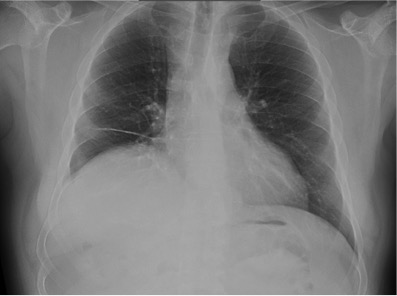

CASO: sospecha de neumonía.

Hallazgos:

- En un principio podríamos decir que existe un aumento de densidad retrocardiaco que podría ser compatible con condensación neumónica a dicho nivel, sin embargo estamos ante una placa poco inspirada, lo cual puede llevarnos a cometer errores diagnósticos.

- Se recomendó volver a realizar la radiografía, observar a continuación:

Ya no se observa el aumento de densidad retrocardiaco, la placa es normal.

INSPIRACIÓN: Una placa bien inspirada es aquella en la que se observar 6-7 arcos costales anteriores o 10-11 arcos costales posteriores. Lo contrario puede producir imágenes falsas de condensaciones o de seudocardiomegalia.